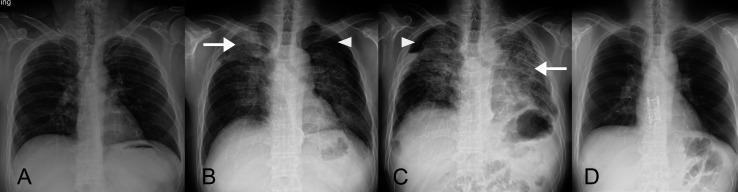

本报告重点关注在厨房台面生产中使用含有高结晶二氧化硅的人造石所带来的职业健康风险。报告一名43岁男子因从事切割和抛光石英石原料的工作而患上严重矽肺。对患者的医疗记录和职业史进行了回顾性分析。根据临床表现、肺功能检查、放射学表现和组织学报告,诊断为严重矽肺、中度限制性肺病和双侧肺气肿。患者接受了肺移植,术后肺功能有所改善。该研究强调了与人造石相关的重大健康风险,并强调了员工和工人意识和保护措施的重要性。临床医生在诊断有职业接触过含有高结晶二氧化硅的人造结石史的患者的呼吸道症状时应谨慎。

This report focuses on the occupational health risks associated with the use of artificial stones containing high levels of crystalline silica in the production of kitchen countertops. It presents the case of a 43-yr-old man who developed severe silicosis due to his occupation involving cutting and polishing quartz stone raw materials. A retrospective analysis of the patient's medical records and occupational history was conducted. The diagnosis of severe silicosis, moderate restrictive lung disease, and bilateral pneumothorax was based on clinical manifestations, pulmonary function test, radiological findings, and histological reports. The patient underwent lung transplantation, and his pulmonary function improved post-surgery. The study highlights the significant health risks associated with procedures involving artificial stones and emphasizes the importance of awareness and protective measures for employees and workers. Clinicians should be cautious when diagnosing respiratory symptoms in patients with a history of occupational exposure to artificial stones containing high levels of crystalline silica.